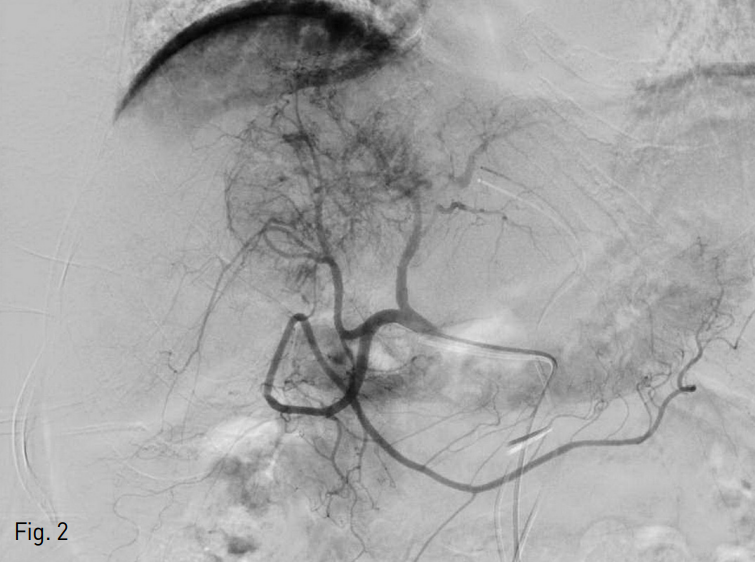

방사선색 전술 시행을 위한 사전 평가를 시행하였다. 우측 총대퇴동맥을 천자하여 4 Fr sheath 3개를 각각 삽입 후 4 Fr Yashiro catheter (Jung Sung Corp., Seoul, Korea) 3개를 사용하여 총간동맥과 좌측 전위 간동맥 (replaced left hepatic artery)이 기시하는 좌측 위동맥 (left gastric artery)에서 혈관 조영술을 시행하였다. 구역 4번의 간동맥이 공급하는 혈관이 풍부한 종양을 확인할 수 있었다 (Fig. 2). 우측 간동맥 근위부의 위이자십이지장동맥 (superior pancreaticoduodenal artery)과 위십이지장동맥 (gastroduodenal artery)을 확인하였고, 방사선색전술 시행시 위장관으로 미세구가 유입되는 것을 방지하기 위해 2.2 Fr microcatheter (Progreat, Terumo, Tokyo, Japan)로 이 동맥들을 미세선택하여 Tornado coil 4개 (3mm/2mm x 1, 4mm/2mm x 3, Cook, Bloomin gton, IN, USA), Nester coil 27H (14cm x 4mm x 2, Bloomington, IN, USA), Interlock detachable coil 27H (8mm x 20cm x 1, 6mm x 20cm x 1, Boston scientific, Natick, MA,USA)를 사용하여 색전술을 시행하였다 (Fig.3).

Fig. 2

Angiogram of right hepatic artery. In the segment 4, hypervascular tumor (about 7.5cm) is shown. The superior pancreaticoduodenal artery from right hepatic artery is identified.